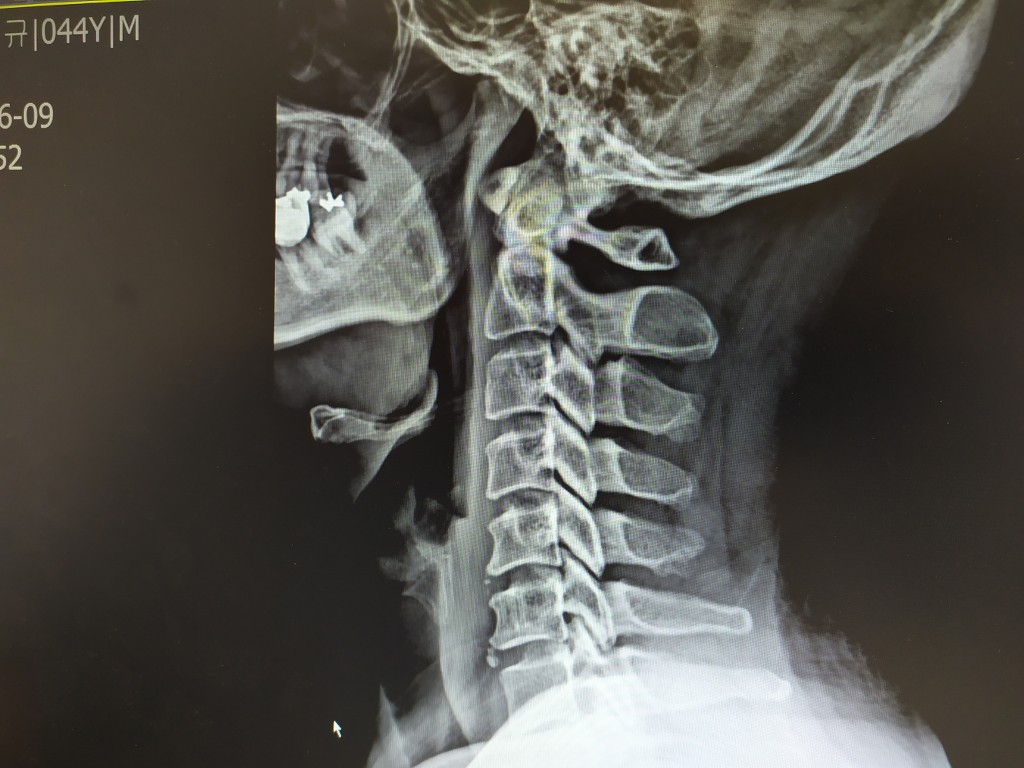

일자목이라고 해서 내가 비교를 해 달라고 하니 아래와 같이 비교를 해주더군요.

좌측이 현재 일자목이라고 판단받은 제 사진이고 우측이 2개월 정도 도수치료 받아 C자형이 되어 가고 있는 분 사진이라고 하네요.

저도 치료 받아 일자목을 C자형태로 만들어 준다고 합니다. ^^ 그러면서 어깨 통증은 염증이 있는데 도수치료로 함께 치료 가능하다고 합니다.